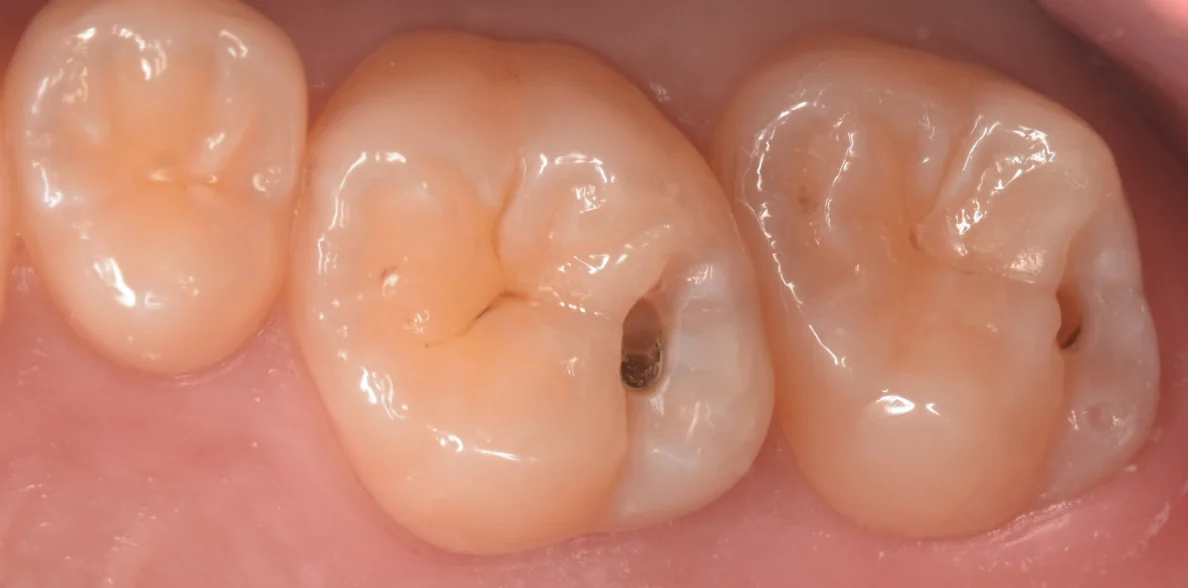

軽く削ってむし歯を見やすくしたのがこちらです。

内部に白いむし歯と黒いむし歯があります。

白いむし歯は「急性う蝕」と言って急速に進行し、内部に深く入り込む虫歯です。

黒いむし歯は「慢性う蝕」と言って緩慢に進行し、横に広がるように進行するむし歯です。

今回は若い方でしたので、急性と慢性の間というか混合しているみたいな状態でしたね。

実際除去し切ったのがこちらになります。

ぱっと見非常に小さい穴ではありますが、実は内部で非常に大きく進行していたため、この見えている穴のおおよそ2倍くらいは内部の歯がない状態になっていました。

1stトリートメントと言って、初回の治療だったため、歯を非常に多く温存することができましたね。